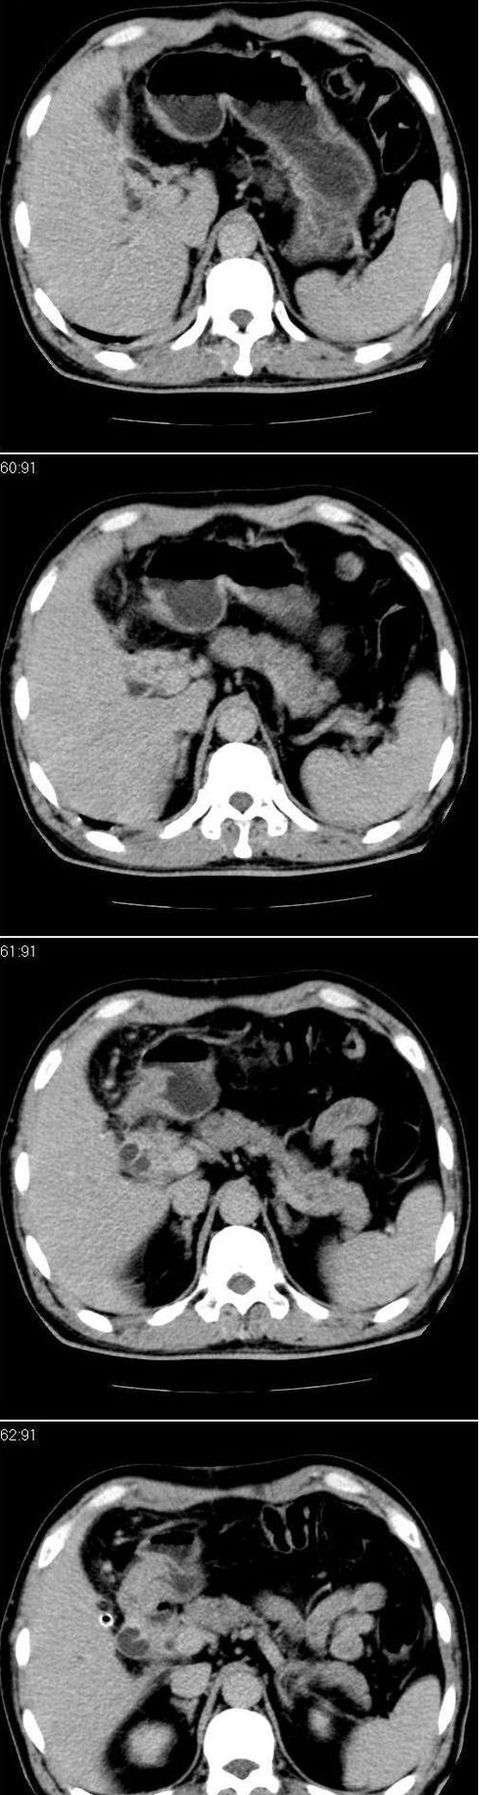

标题: CT13147:男,57岁。因胆结石阻塞性黄疸入院。 [打印本页]

标题: CT13147:男,57岁。因胆结石阻塞性黄疸入院。

男,57岁。因胆结石阻塞性黄疸入院。这是胆囊切除术后的照片,看看此片到底有什么问题。

胆总管有没有问题,尤其是肝门附近的胆总管?

肝门附近的胆总管轻度扩张 请楼主复习术前片

在手术切除胆囊的过程中,发现肝门部胆总管恶性占位,因为家属不同意手术,没有切除,能看出来么?

肝内外胆管轻度扩张,胆囊窝内见引流管考虑胆囊切除术后改变.胃窦部软组织似增厚,建议胃镜检查.

肝内外胆管轻度扩张。楼主提示左右肝管合汇区域壁稍厚。胆总管末段壁似也稍厚有轻度强化。就现有资料诊断难。